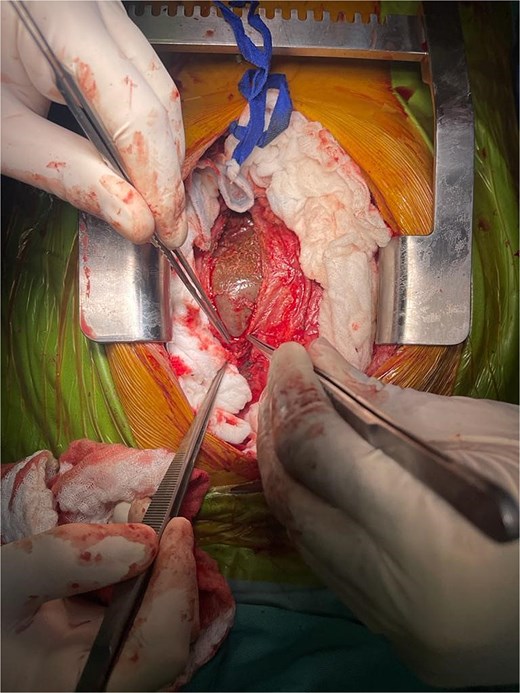

A diagnosis of right-sided heart failure due to an intrapericardial mass was made. The cardiothoracic surgery team performed urgent surgery through a small chest incision. During the operation, a large cystic structure measuring ~ 6 by 7 cm was found inside the pericardial sac and was completely removed (Fig. 4). Around 800 cubic centimeters of bloody fluid from the pericardial sac and pleural cavities was drained. Tissue analysis confirmed the diagnosis (Fig. 5).